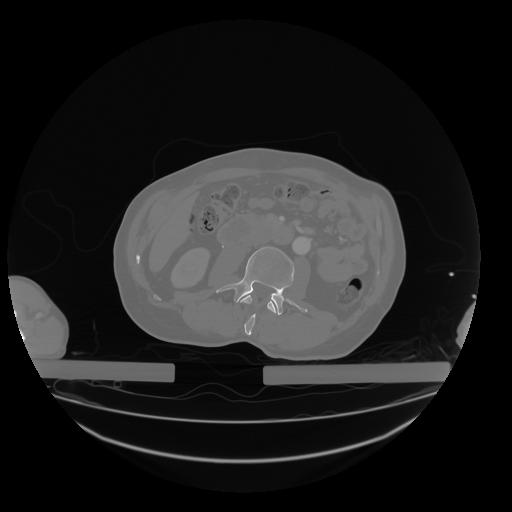

28 CUERPO,CE,Vol,2.0,CUERPO,,